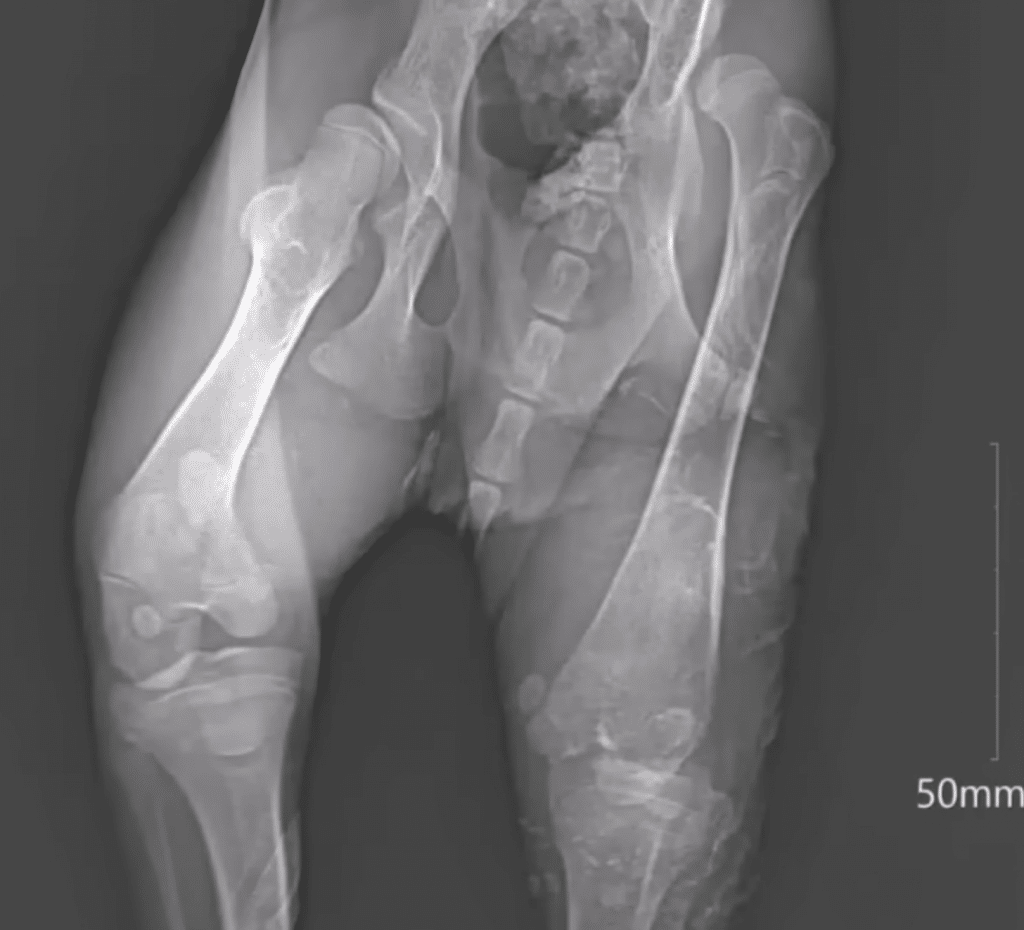

At the veterinary clinic, the reality of Bonbon’s past became clear. Old fractures and physical deformities told the story of long-term hardship. His body was fragile, and recovery would take time.